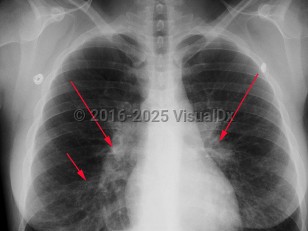

Mycoplasma pneumonia

Mycoplasma pneumonia, also called atypical pneumonia and "walking pneumonia," is a community-acquired pneumonia caused by Mycoplasma pneumoniae. Mycoplasma are pleomorphic, filamentous bacteria that lack a cell wall, are of a smaller size, and possess different genetic features than other bacteria. Of all the Mycoplasma spp isolated from the respiratory tract, M pneumoniae is the most frequent cause of human disease.

Mycoplasma pneumoniae is a common cause of pneumonia and may be responsible for up to 20% of all pneumonias in the general population and 30%-50% of pneumonias in specific closed populations such as those in military barracks and on college campuses. Infection is most common in those younger than 20, although it is seen in all age groups. The disease is seen throughout the year, with a slight increase in incidence in the fall and winter.

Patients typically present with a dry, sometimes paroxysmal, cough; fever; headache; and malaise. They generally appear well to moderately ill and are rarely toxic appearing. Up to 50% of patients also present with upper respiratory involvement with a sore throat and earache. Hemorrhagic or bullous myringitis may be seen in those presenting with an earache. Mycoplasma exanthems frequently occur and can be a diagnostic clue.